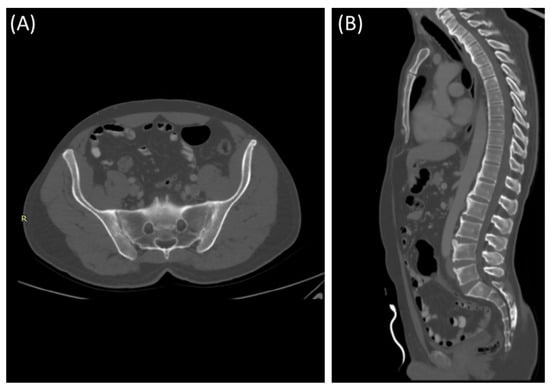

Sacroiliitis is the inflammation of the sacroiliac joint, the largest axial joint in the human body, contributing to 25% of lower back pain cases. It can be detected using various imaging techniques like radiography, Magnetic Resonance Imaging (MRI), and Computed Tomography (CT) scans. Treatments range from conservative methods to invasive procedures. Recent advancements in artificial intelligence offer precise detection of this condition through imaging. Treatment options range from physical therapy and medications to invasive methods like joint injections and surgery.